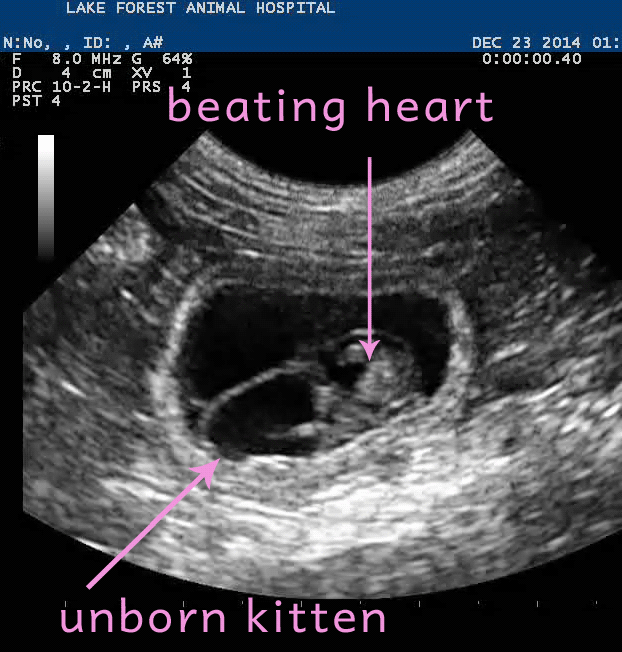

Завораживает, котенок в утробе матери!

Если присмотритесь, то увидите сердцебиение, пока еще нерожденного котенка. Ему где-то 21-24 дня!